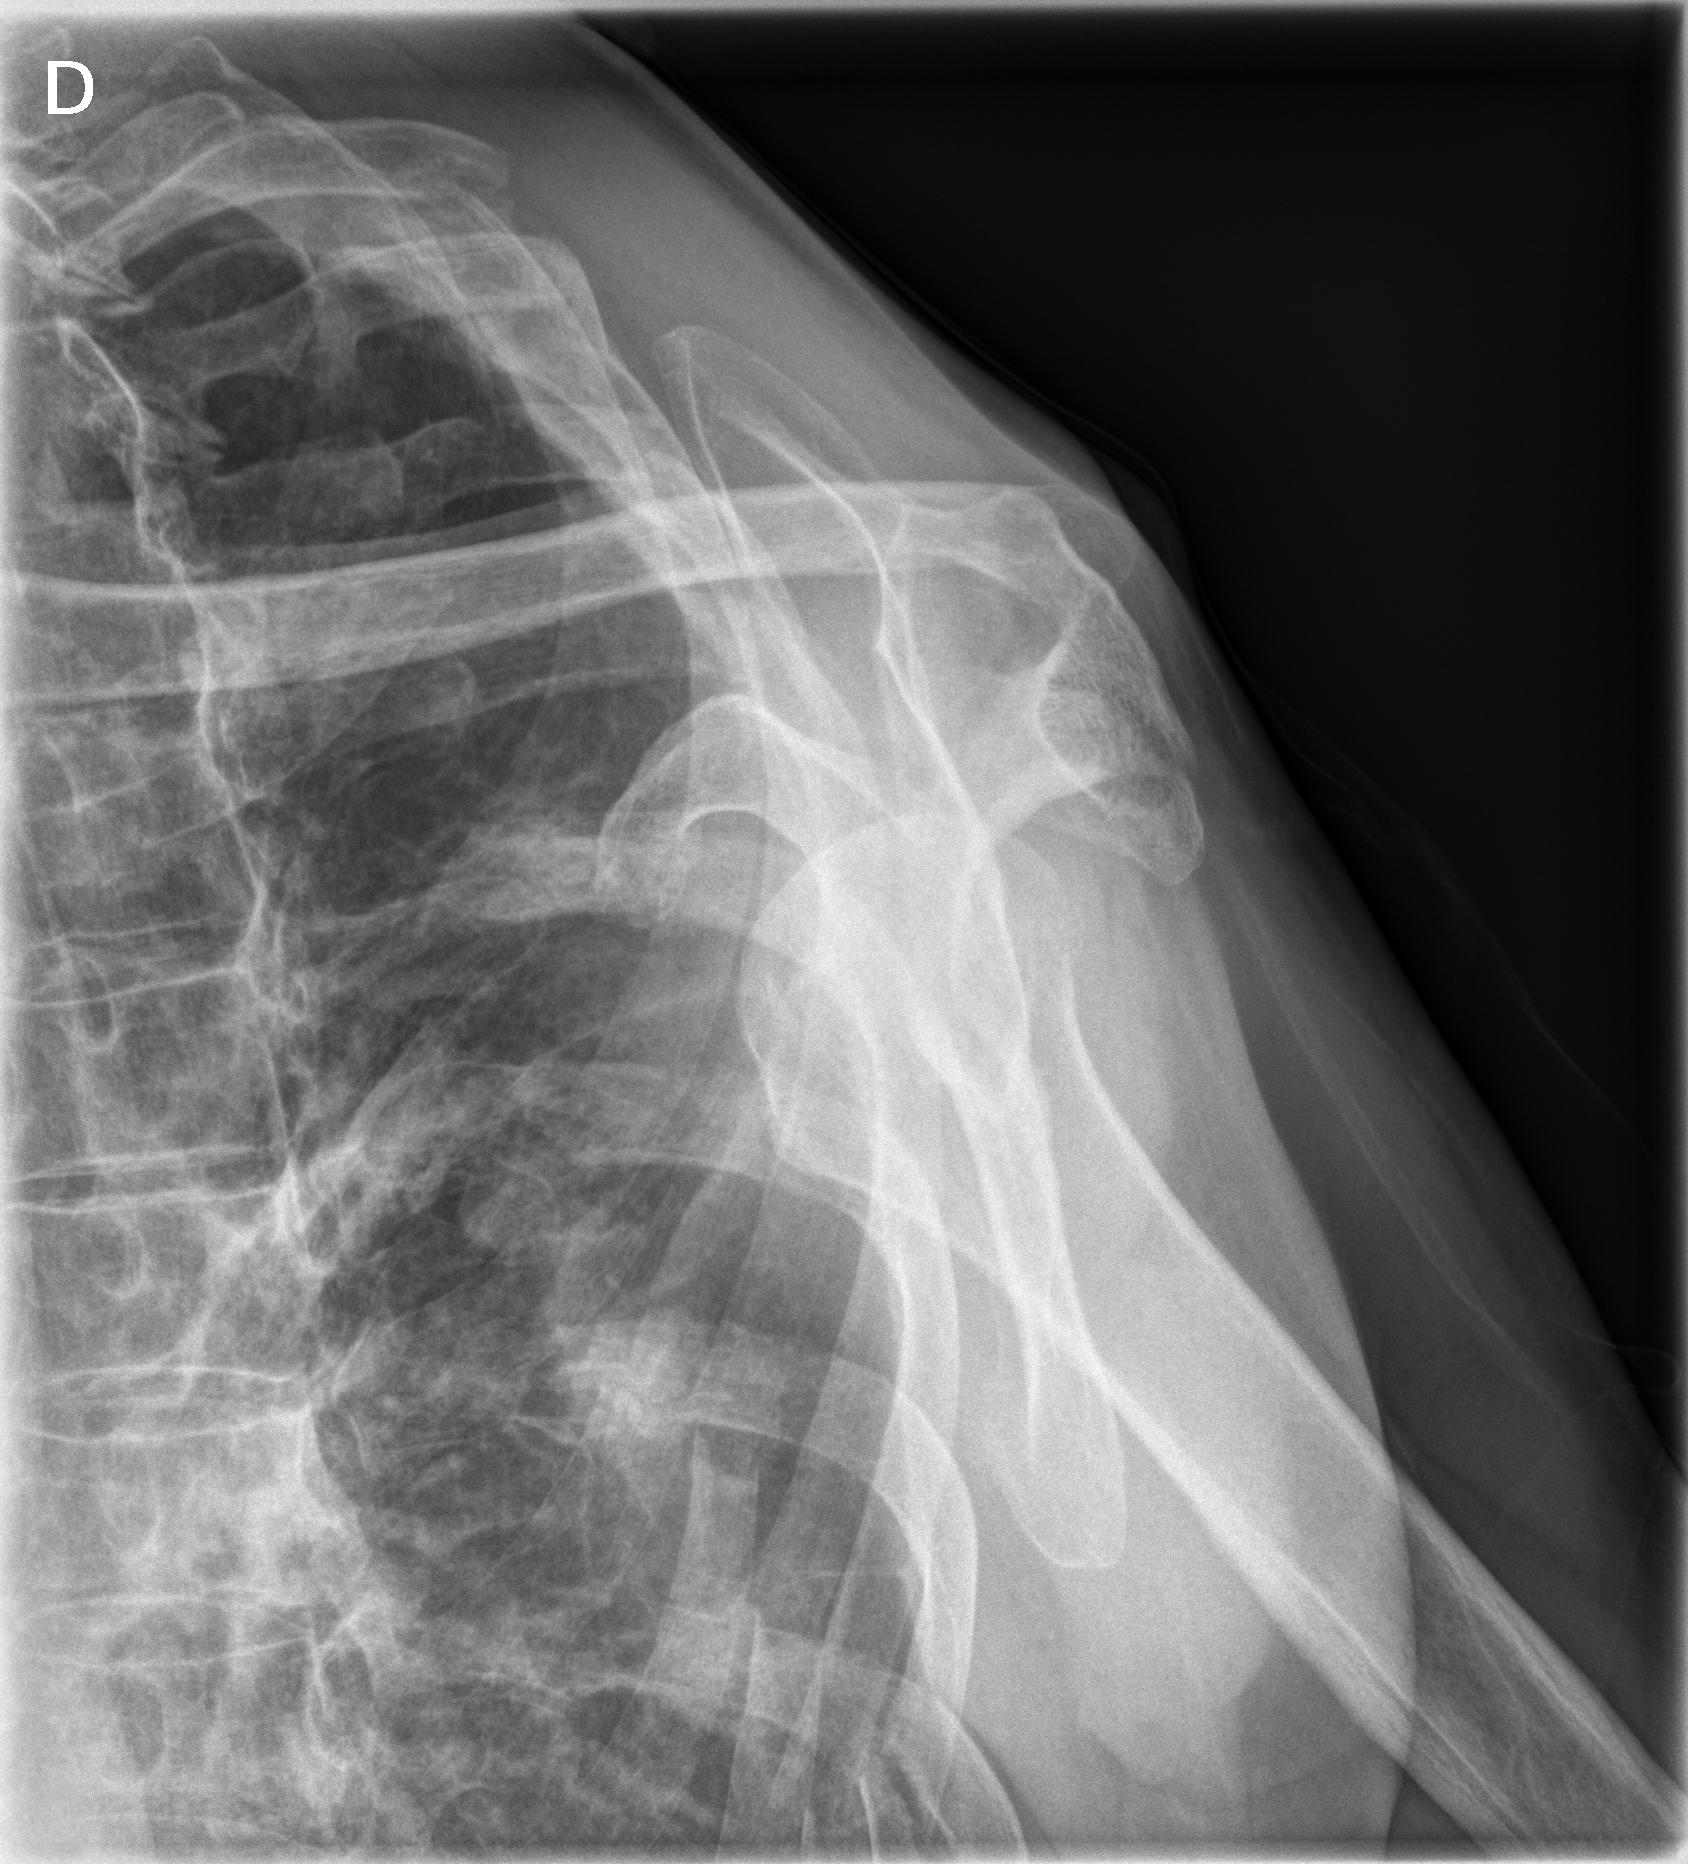

1 Hombro der.